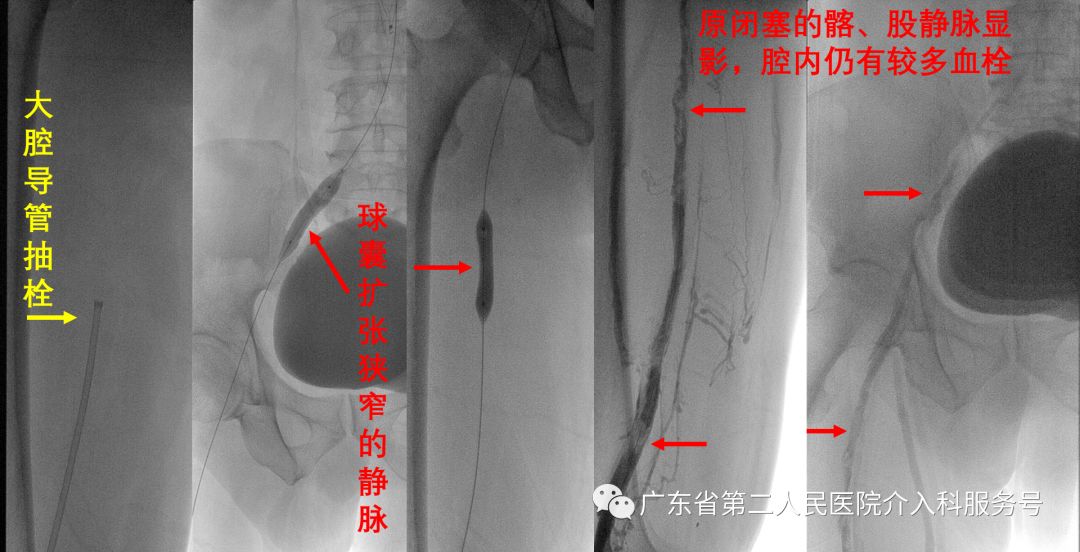

经全科讨论,认为冯先生左下肢深静脉血栓为慢性血栓形成并急性发作堵塞导致左下肢肿胀与疼痛,以陈旧性血栓为主,并决定给予大腔导管抽栓与球囊扩张治疗。

第一次大腔导管抽栓与球囊扩张狭窄的静脉后造影显示:原闭塞的髂、股静脉显影,腔内仍有较多血栓(如下图)。